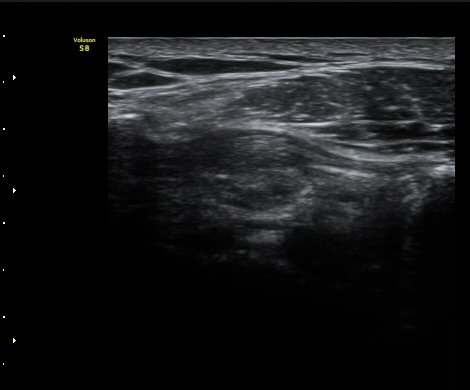

±Ø»ó°Ç Á¾´Ü¸é°Ë»ç½Ã ±Ø»ó°ÇÀÇ Ç¥Ãþ¿¡¼­ °üÂûµÇ´Â °ßºÀ¿À±¸µ¹±â Ⱦ´Ü¸é°Ë»ç»ó¿¡¼­

ÀδëÀÇ ºñÈİ¡ °üÂûµÈ´Ù(»çÁø 4). ±Ø»ê°ÇÀÇ Á¾´Ü¸é°Ë»ç¿Í Ⱦ´Ü¸é°Ë»ç¿¡¼­ ±Ø»ê°Ç ½ÉÃþ¿¡

Àú¿¡ÄÚ º´º¯ÀÌ °üÂûµÈ´Ù(»çÁø 5, 6).